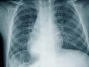

Ne yazık ki KOAH, tanısı ihmal edilen bir hastalık. Toplumda yeterince bilinmiyor ve önemsenmiyor. Halbuki erken tanı ve müdahale, hastalığın gidişini durdurabilir ya da yavaşlatabilir. Tanıda öncelikle hastanın şikayetleri değerlendirilmekte ve solunum fonksiyon testleri ile akciğer grafisi gibi tetkiklerden yararlanılmaktadır.